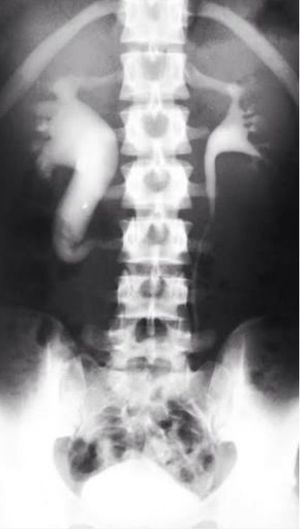

rt kidney hdn may be due to obstruction of ureter with a stone inside and back pressure changes are seen

This is HDN and you are right it is due to urter obstruction but NOT DUE TO STONE but due to IVC(ivp shows fish hook or reverse J sign)a congenital condition known as RETROCAVAL URETER in which rt. Side ureter goes from post. Side of IVC and get compressed leading to HDN and HDU. Treatment :- ureteric relocation ......& Complication :- Angulation of ureter